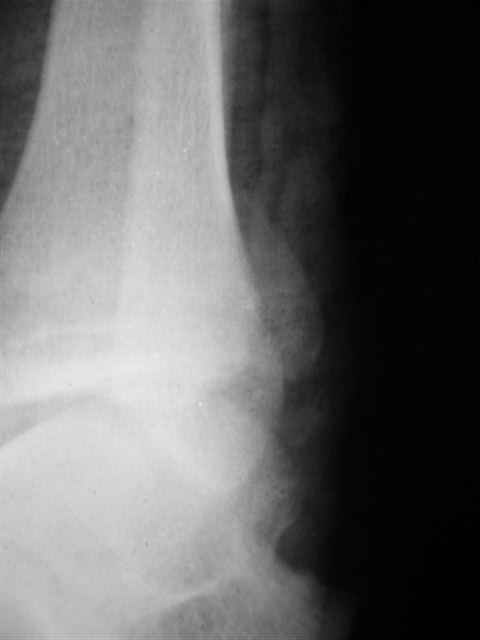

Уважаемый Иван,

Я предупреждал, что ничего сверхъестественного. Каюсь, что одна из спиц прошла несколько дальше, чем нужно было, но главное - перелом стабилизирован и больной работает суставом в полном объёме, несмотря на представленную раннее травму коленного сустава.